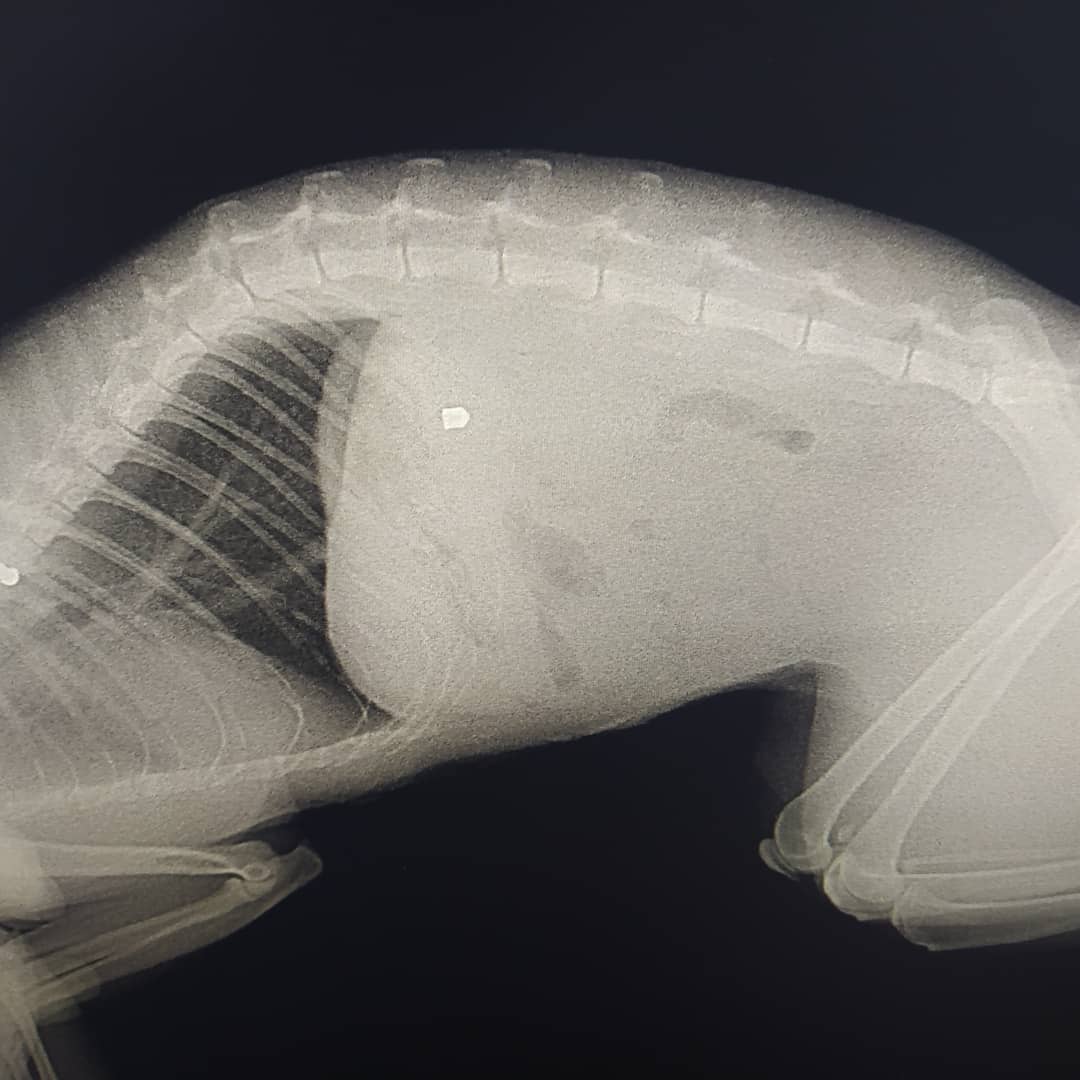

Об этом в Instagram сообщает местная жительница, ее коту прострелили селезенку.

“Вчера кот вечером пришел с раной на животе. Мы повезли его в клинику. Там сказали, что это выстрел с воздушки и что мы не первые, кто к ним обращается с такой проблемой с нашего района”, - говорится в сообщении.

Это уже восьмой подобный случай в районе. Коту оказали помощь, затем провели операцию в другой больнице. Воздушка оказалось необычной, шансов было всего 20%. К счастью, все прошло успешно, но коту понадобится много времени на восстановление.